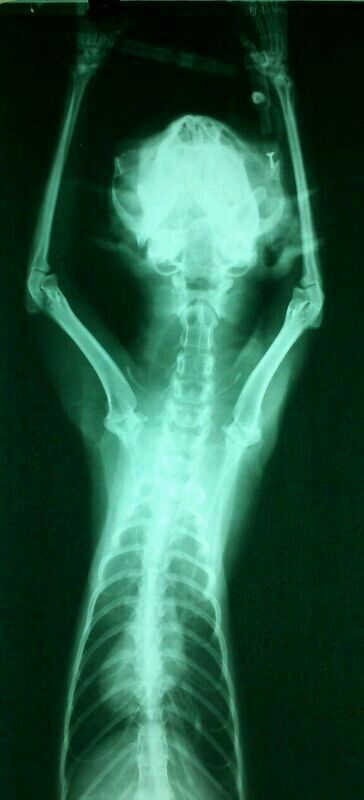

預計鼻胃管餵插管,插管後的x光檢查後發現鼻胃管無法進入食道

轉診其他醫院確診沾黏,建議安樂死

愛心媽媽不忍,自費帶至其他醫院預計進行食道切除重建手術